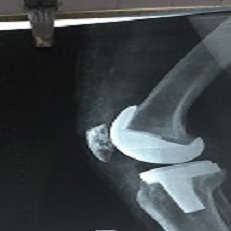

Tkr 69 Year Old

Tkr 73 Year Old